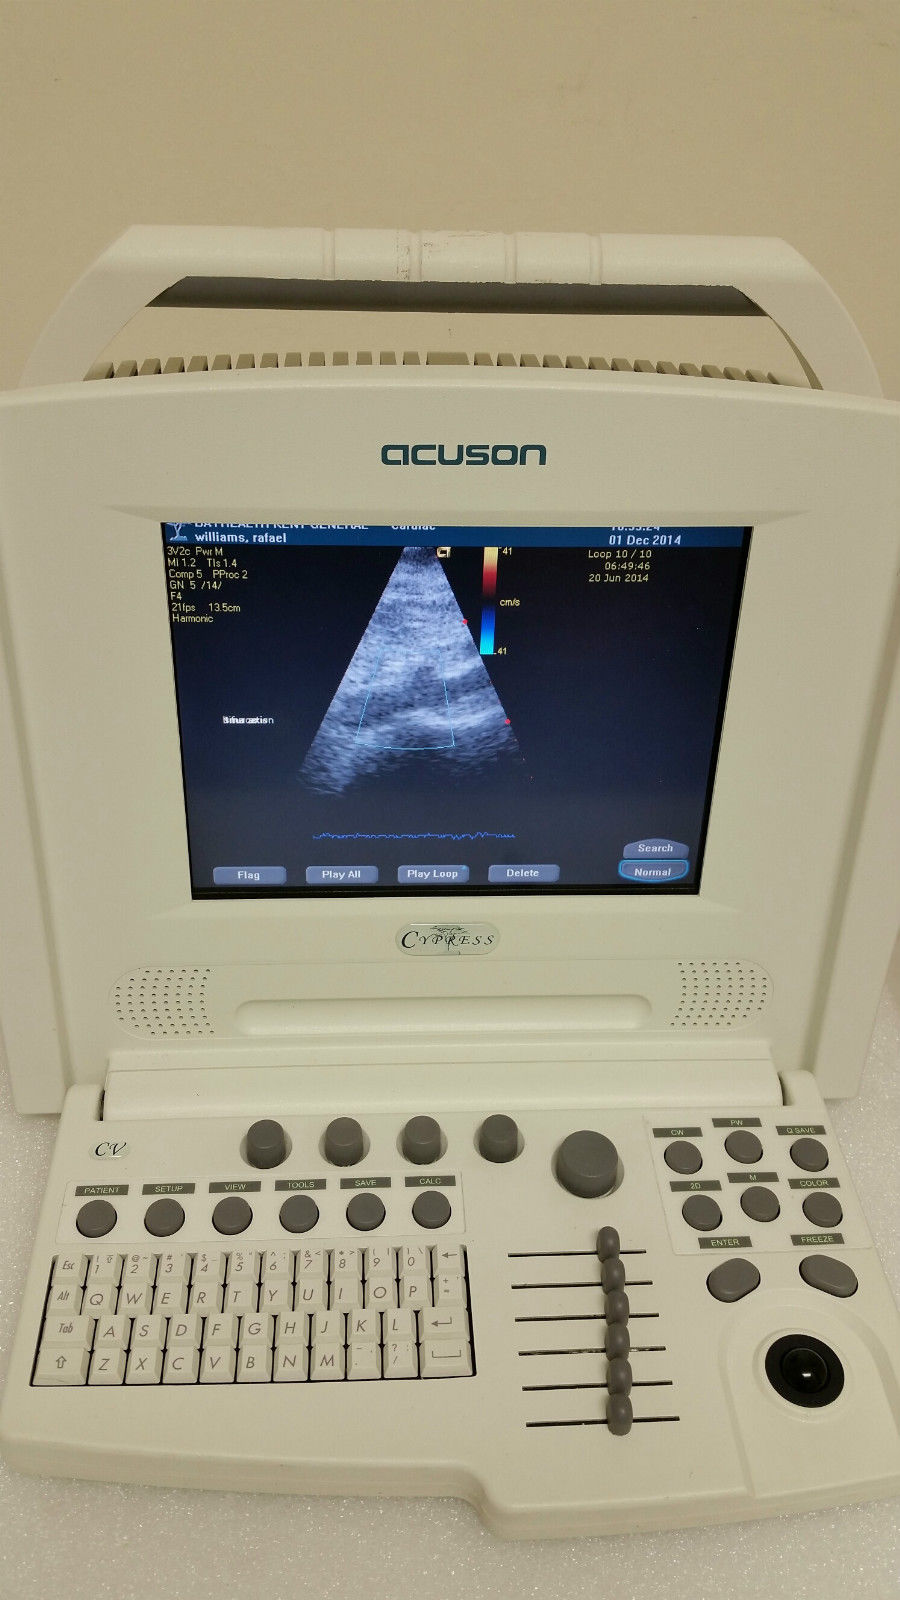

Explore the Acuson Cypress Cardiac Vascular Ultrasound Machine

Seller Notes:âExcellent condition, see photos.â

The Acuson Cypress Cardiac Vascular Ultrasound Machine is engineered for exceptional imaging and diagnostic accuracy. Its advanced technology allows for detailed visualization of cardiac and vascular structures, which is essential for healthcare providers. The inclusion of the 3V2c and 7L3 probes enhances its versatility, making it suitable for various clinical applications. As a result, this machine is a crucial tool in modern cardiology and vascular assessment.

Enhanced User Experience

With a user-friendly interface, the Acuson Cypress simplifies the entire operation process. Health professionals can navigate through its features effortlessly, thanks to the intuitive design and layout. This ease of use not only speeds up the workflow but also improves the overall user satisfaction. Therefore, healthcare practitioners spend less time on technicalities and more on patient care and diagnostics.

Robust and Reliable Performance

Designed for durability and efficiency, the Acuson Cypress guarantees reliable performance in fast-paced clinical environments. Its robust features withstand rigorous daily use while maintaining high-quality imaging standards. Additionally, the machine's consistent performance over time helps healthcare facilities reduce unexpected downtime and maintain patient trust. Thus, investing in the Acuson Cypress is a smart decision for any medical institution aiming for excellence in diagnostics.